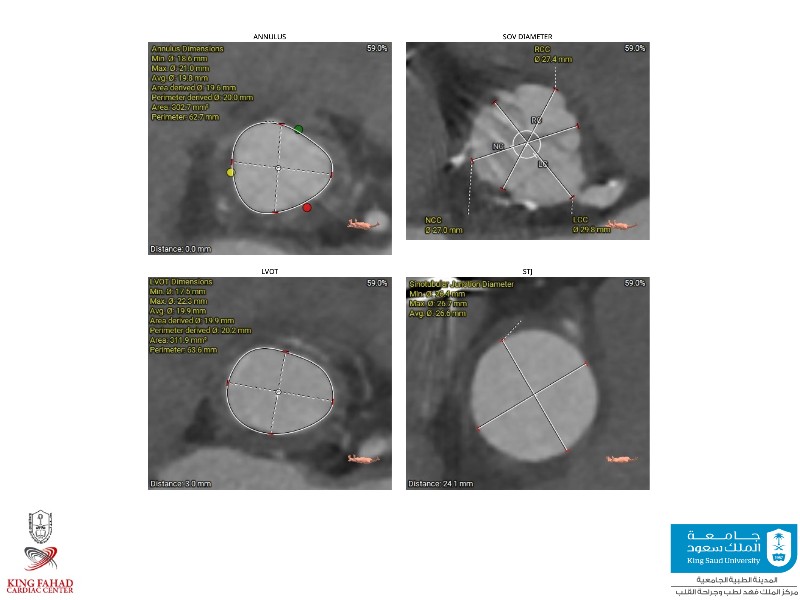

This session helps you anticipate and address complex scenarios such as mitral valve-in-valve, TAV-in-SAV, and valve-in-valve-in-valve procedures. Learn from expert case discussions that explore procedural strategies, technical challenges, and best practices to optimize outcomes in redo structural heart interventions.

- To anticipate and manage second valve scenarios with SAPIEN 3 Ultra RESILIA, including mitral valve-in-valve, TAV-in-SAV, and TAV-in-TAV

- To understand procedural strategies and challenges in complex redo scenarios using SAPIEN 3 Ultra RESILIA